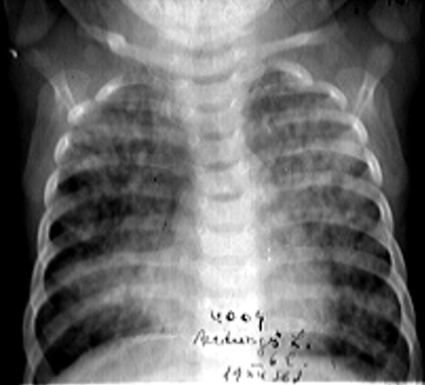

DESCRIERE:

DX: hiperplazie timică bilaterală

DD: